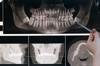

The success of implant placement hinges on adequate bone density and overall oral health. Prior to surgery, a comprehensive evaluation—including 3D imaging and bone density tests—is conducted to determine candidacy. Patients with insufficient bone may require a preliminary procedure, such as a bone graft, to strengthen the jaw. For adults over 65, this step is particularly crucial, as age-related bone loss can compromise implant stability. Smoking, a known inhibitor of osseointegration, is strongly discouraged during the healing phase, which typically spans 3–6 months.

Dentists use a precise and multi-step process to place a fake tooth, also known as a dental implant or prosthetic tooth. The procedure typically begins with a thorough examination and consultation to determine the best type of implant for the patient's needs. Once the implant type is chosen, the dentist will surgically place a titanium post into the jawbone, which acts as the root of the new tooth. Over several months, the post fuses with the bone in a process called osseointegration, providing a stable foundation for the artificial tooth. After the post has fully integrated, an abutment is attached to connect the implant to the prosthetic tooth. Finally, a custom-made crown, designed to match the patient's natural teeth in shape, size, and color, is securely placed onto the abutment, restoring both function and aesthetics to the patient's smile.